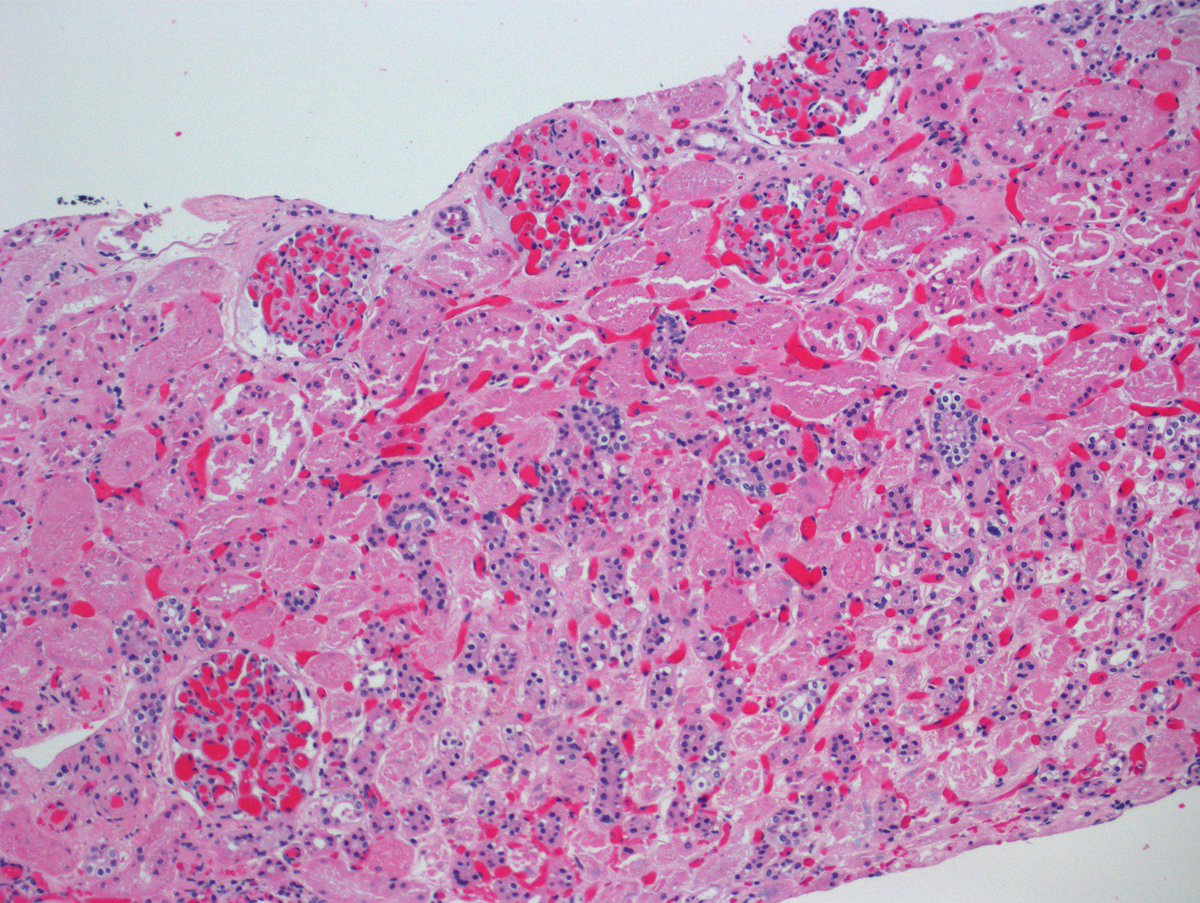

Time-zero

#transplant biopsy showing impressive congestion and tubular necrosis. Got worried so I called the transplant team. No perfusion on nuclear medicine scan. Nephrectomy showed renal vein thrombosis (parenchyma in second pic).#RenalPath pic.twitter.com/F6Jo9LUeG3